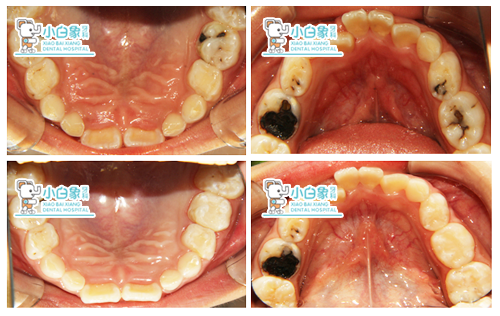

74 75 邻合面龋坏达牙本质深层,温度测试同正常牙,牙龈无红肿。

54 55 84 85 龋坏

54 55 84 85 牙体缺损

54 55 84 85 去腐探查